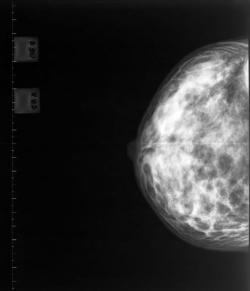

A new study shows that younger women aged 40 to 49 who undergo screening mammograms are diagnosed with breast cancer at an earlier stage and with smaller tumours.

The research, carried out by University Hospitals in Cleveland, USA, also found that screening mammograms were more likely to identify lesions on the breast that are not cancerous, but are linked to a higher risk of breast cancer.

The study was recently published in the American Journal of Roentgenology and supports BCAC’s view that women should start getting regular mammograms from the age of 40.

The researchers examined 108 breast cancers found by biopsy in women aged 40 to 49 and discovered that that 71 per cent of the cancers were diagnosed in women undergoing regular mammograms, while only 37 per cent of the cancers were diagnosed in women who had not been screened.